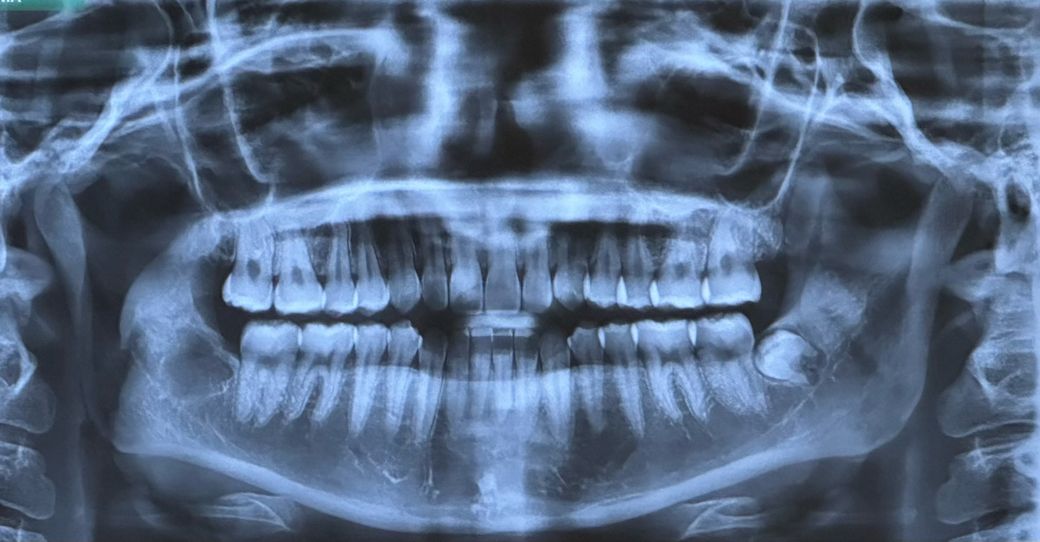

첫번째 사진이 최근이고 두번째가 일년전인데요

• 1번 째 사진

파노라마는 턱관절을 관찰하기에 적절한 방사선사진은 아닙니다만 위 사진상에는 괜찮아보입니다.

엑스레이 상으로는 턱관절 과두가 날카롭게 보이긴 합니다. 정확한건 치과에 가셔서 턱관절 CT를 찍어보셔야될것같습니다.

1. 턱관절엔 큰 변화나 병적인 양상은 없어보입니다

2. 어떤 통증을 느끼시는지 명확히 서술되진 않았으나 꼭 턱관절 때문이 아니라도 왼쪽 아래 매복 사랑니때문에 턱 통증, 입 안벌어짐, 씹을때 통증 등이 있을 수도 있습니다